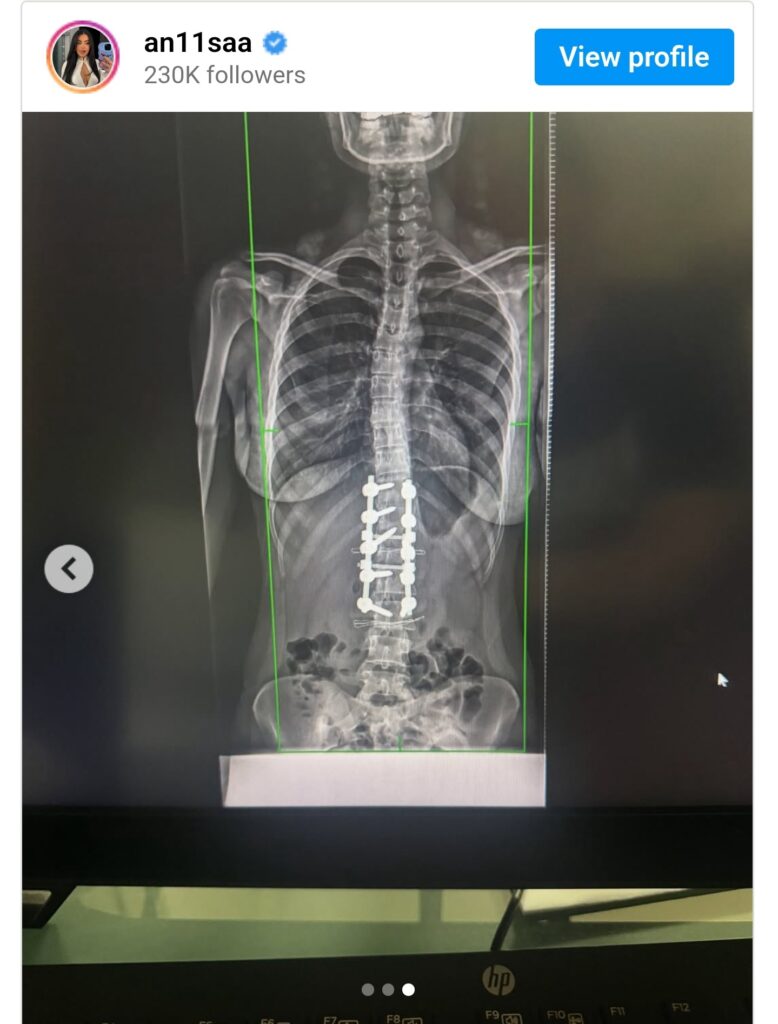

Ish banorja e BBVK i është nënshtruar operacionit për skoliozën.